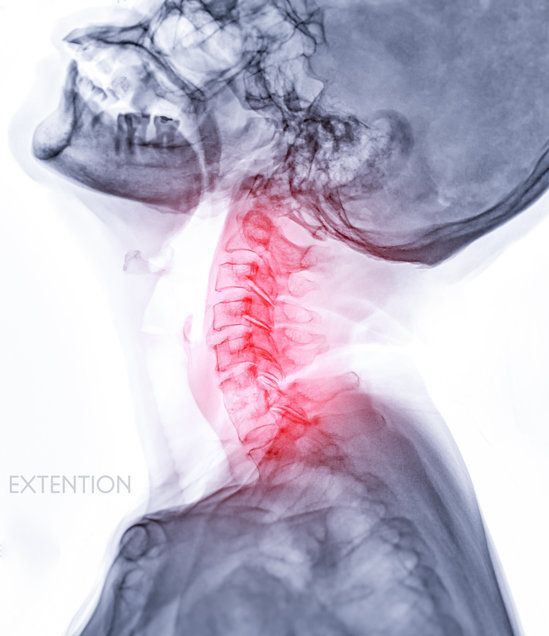

기사와 직접 관련 없는 자료사진 (게티이미지)

정밀 검사 결과, 하품의 힘으로 경추 6·7번이 압박돼 돌출된 것으로 확인됐다. 의료진은 “매우 드문 사고”라고 했다.